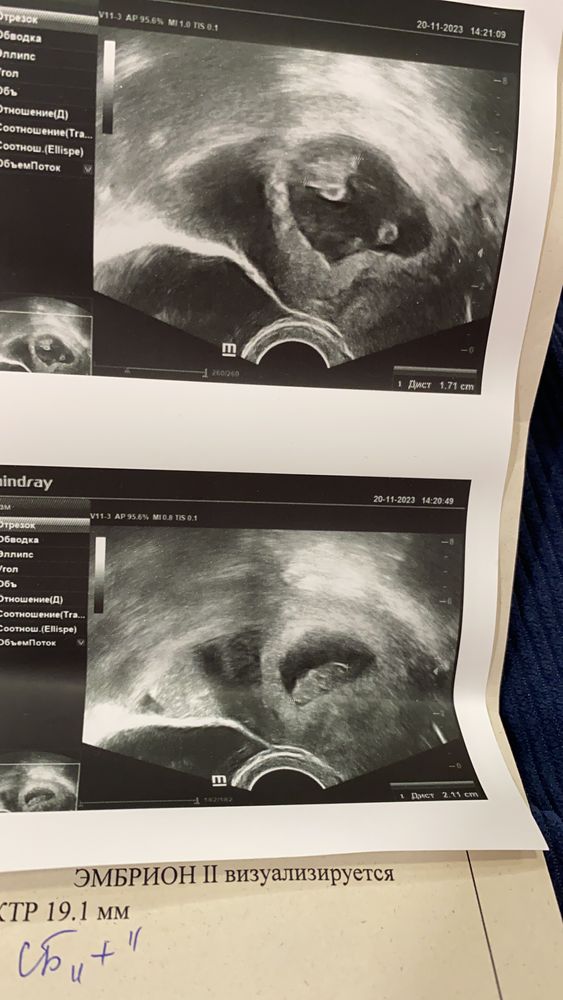

Таня, Изображение Изображение

Таня, у вас монохориальная двойня, как и мои! Тоже располагались напротив друг друга. Перегородку нужно найти с 10 недель, ее уже видно будет. И тогда подтвердят амниальность, будут ли в одном мешочке или каждый в своём. Но плацента у таких двоен одна. А так поздравляю вас с таким событием!😍

Юлия, теперь я поняла, что этот черный овал в центре (с 2мя эмбриончиками) -это не матка, это и есть плодное яйцо 🙈😅 а матка - серая толстая вокруг. Спасибо, что помогли разобраться 🙏🏻